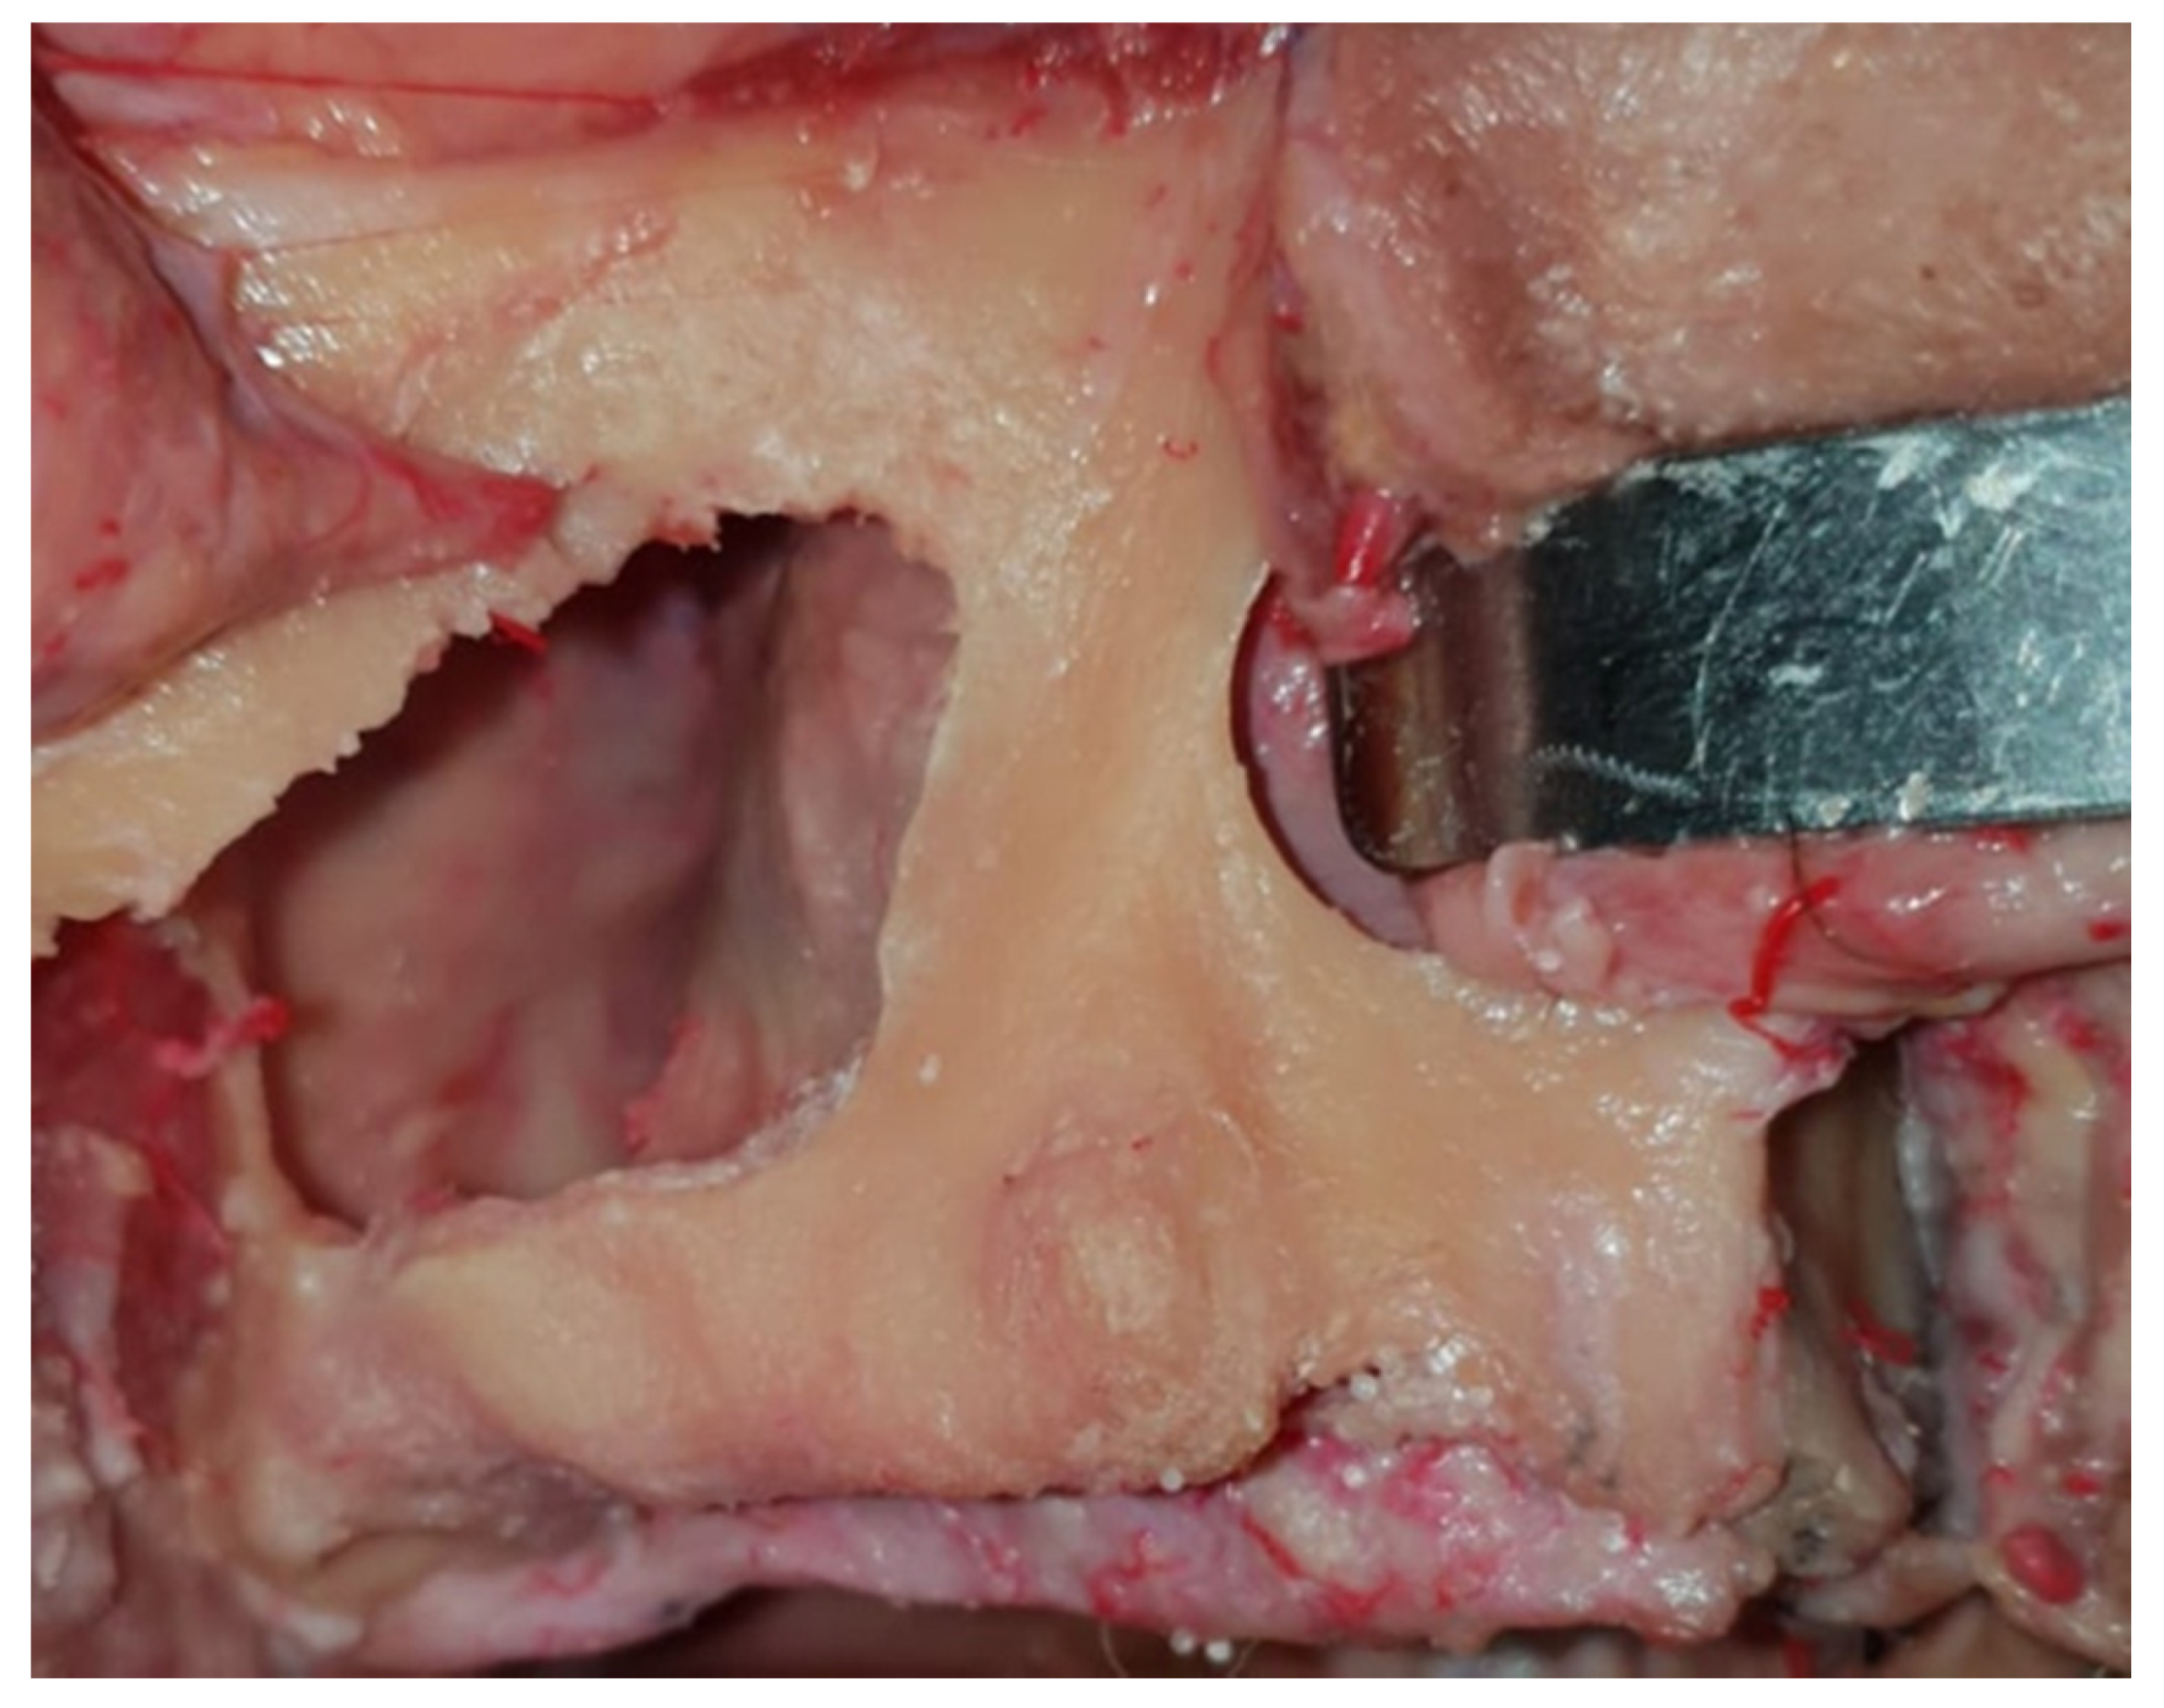

2.2. Virtual Iuxtameatal Implant Positioning